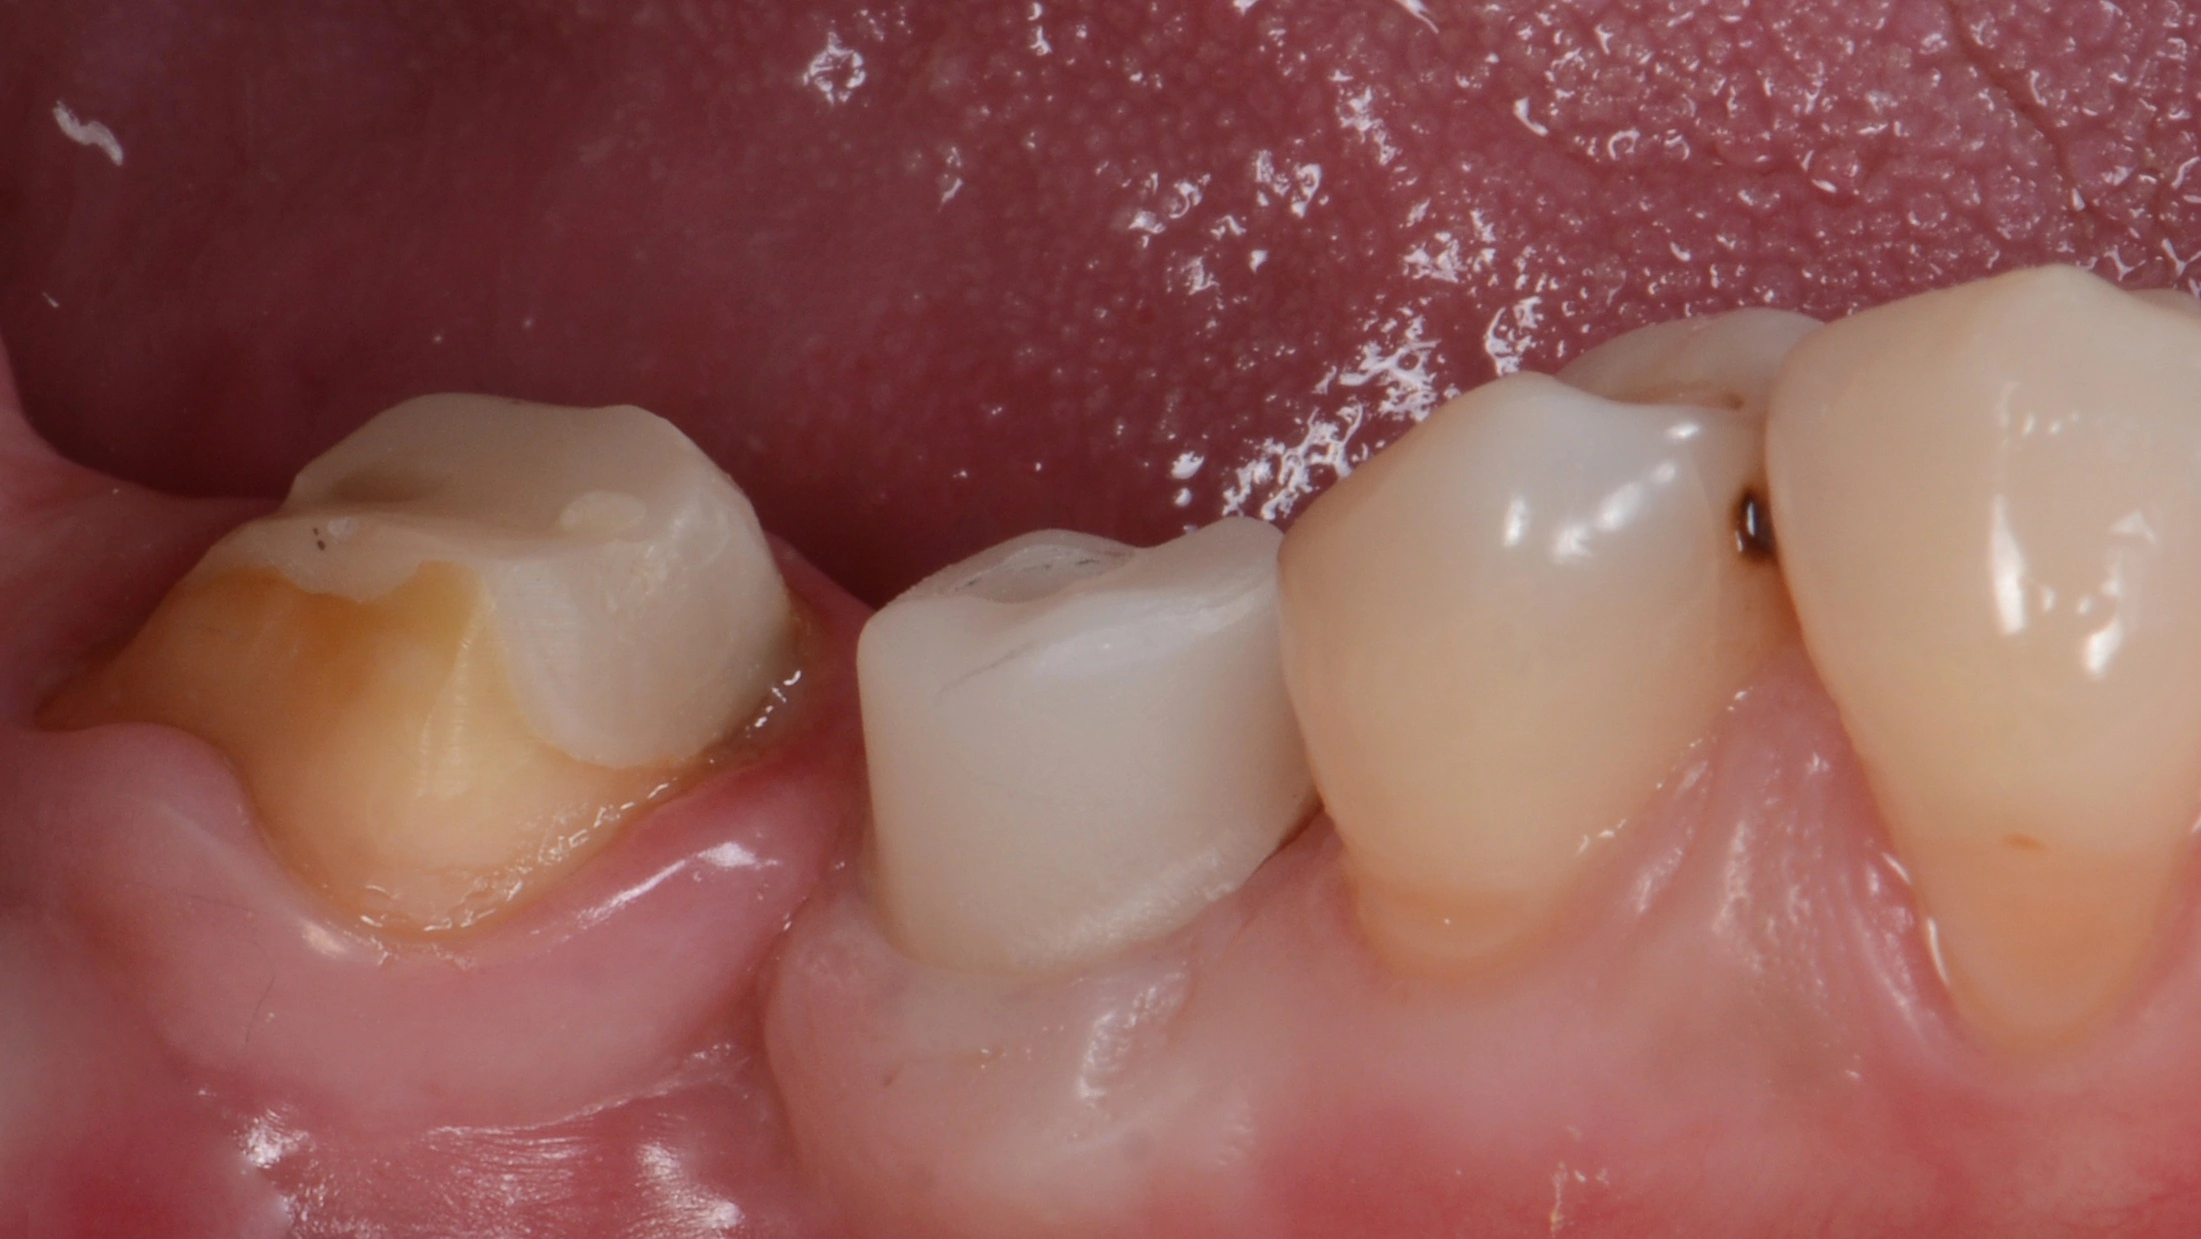

Далее провизорное протезирование с препарированием зуба 47, и после формирования профиля постоянное протеизрование коронками на цементной фиксации на имплантате и на зубе. Зачастую, не всегда вижу необходимость в апрайте семерок, особенно, если в дальнейшем их еще и требуется покрыть коронкой.